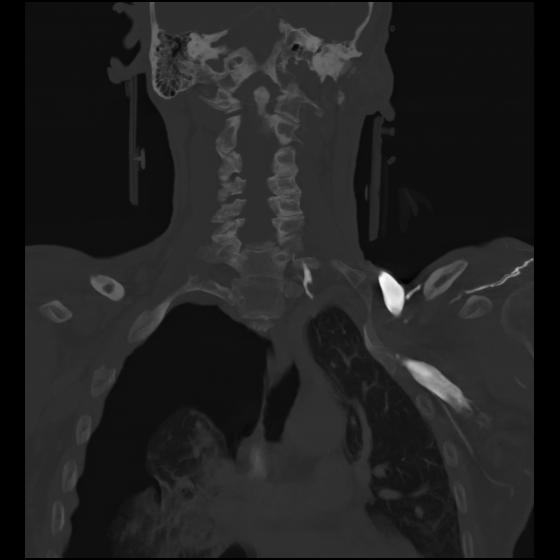

23 ANGIO,CE,Cor-MIP,5.000,ANGIO,Cor-MIP,